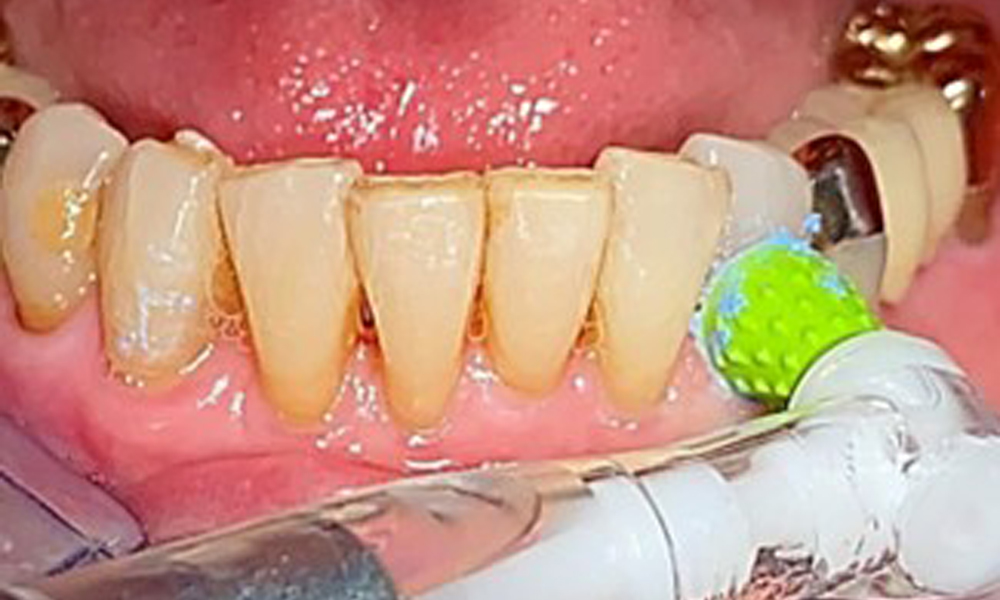

Frontal view with the maxillary denture in situ.

Fig. 1: Frontal view with the maxillary denture in situ.

The patient was fitted with a combined removable maxillary telescopic prosthesis more than 25 years ago (Fig. 1, Fig. 2, Fig. 3) and is very happy with her dentures. The patient has an adequate fixed denture for the mandible (Fig. 4).

A single-tufted brush is specifically recommended for the telescopic prostheses (Fig. 8) and the patient should be advised on the appropriate interdental brush size (Fig. 9). The patient has been implementing these recommendations for intraoral hygiene at home for many years and was encouraged to continue during the professional preventive dental appointment.

Illustration of a single-tufted brush for home care of the implants and telescopic prostheses.

Fig. 8: Illustration of a single-tufted brush for home care of the implants and telescopic prostheses.